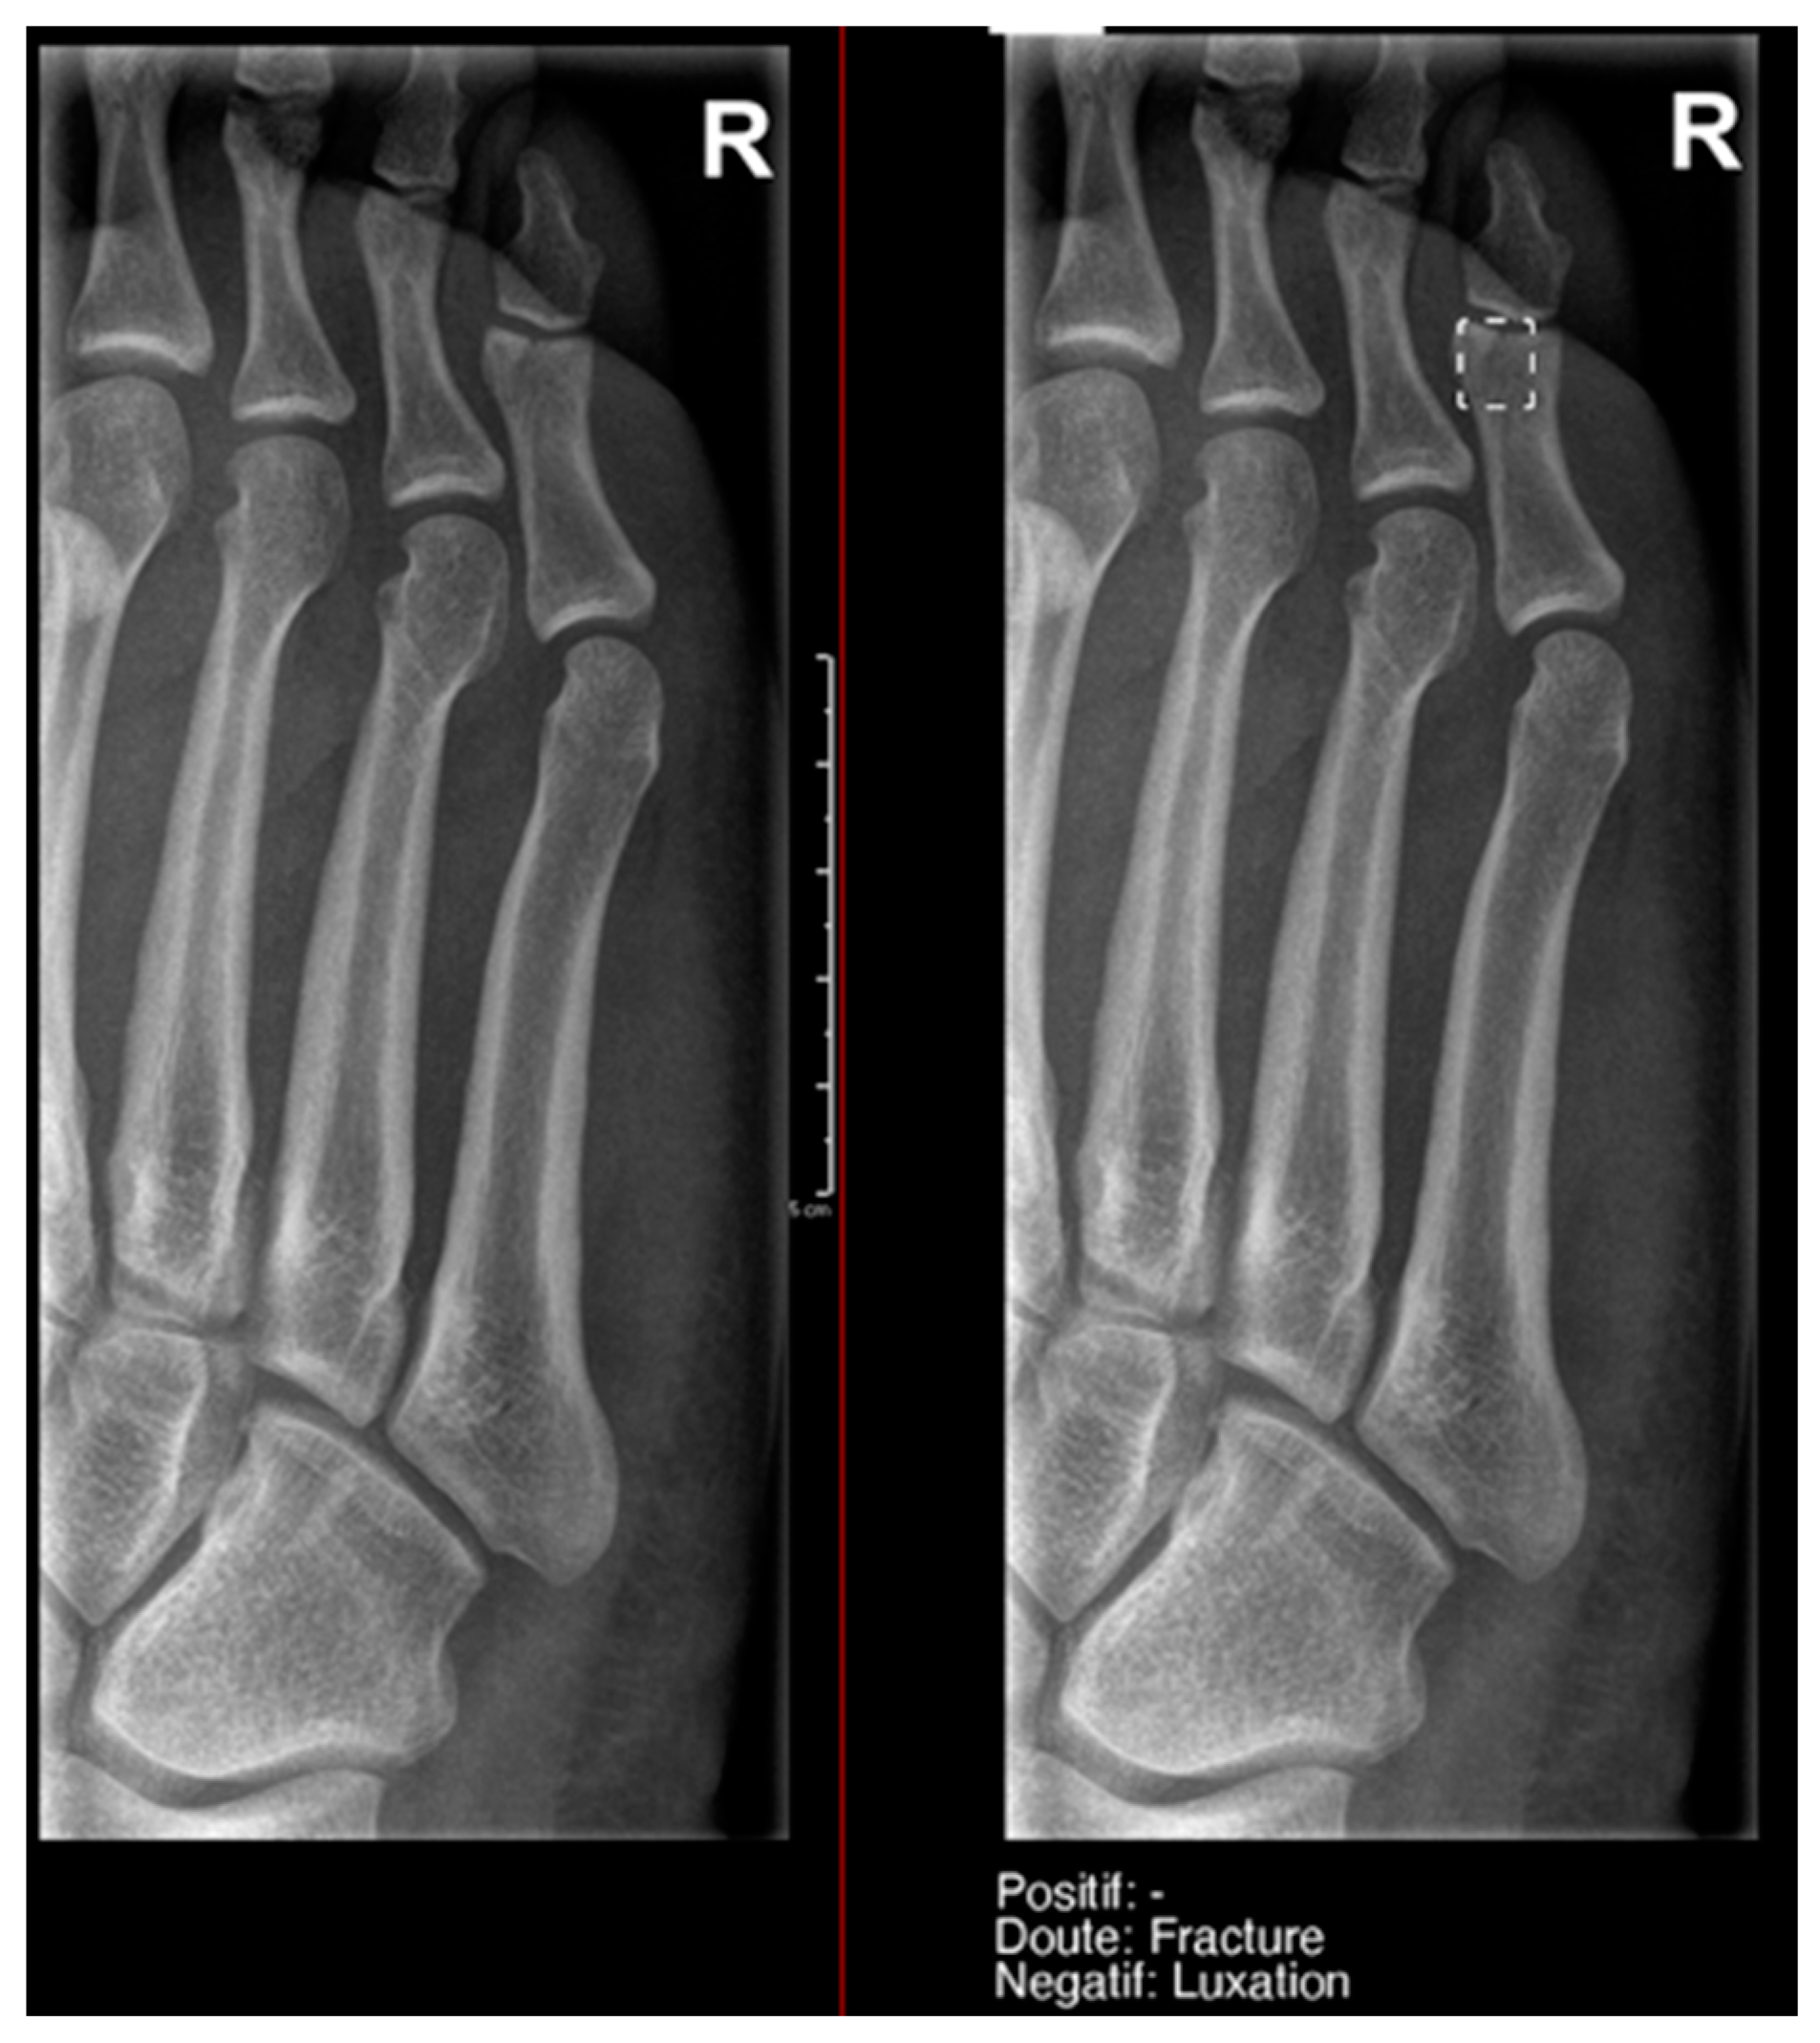

What we found particularly noteworthy was that in the overall group, we recorded 12 doubts by the resident, and 50% of them were confirmed by the gold standard. Milvue provided a higher number of doubtful cases—58 cases—but the proportion of positive cases was lower (only 25.9%) (Figure 7).

Figure 7.

Example of a doubtful fracture marked with a dashed-line box on the AP knee radiograph, which corresponded to a Pellegrini–Stieda lesion.

This difference in the positivity of cases marked as doubtful was influenced by the presence of anatomical variants in the following:

- Ankle and foot: On six occasions, Milvue marked the fracture variable as doubtful in cases with a bipartite medial sesamoid (two patients), an accessory sesamoid at the base of the 5th metatarsal, synphalangism, os peroneum, and os naviculare. (Figure 8).

Figure 8. Example of an anatomical variant (bipartite hallux sesamoid), which was recorded as doubt fracture by AI and as negative by the radiology resident. - Hand: Milvue marked the fracture variable as doubtful in the case of multiple accessory ossicles.